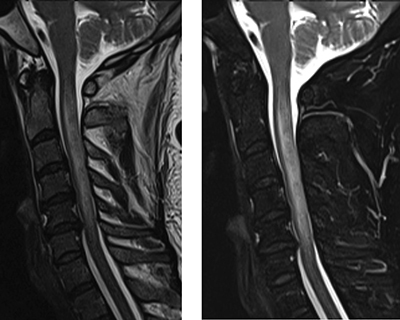

Spinal cord sarcoidosis is a rare condition that can present as a longitudinally extensive transverse myelitis. Current imaging may suggest this pathology, but the final diagnosis relies on the histologic findings. Teaching point: Considering neurosarcoidosis in the differential diagnosis of longitudinally extensive transverse myelitis.

Abstract Image